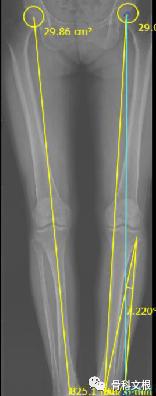

HTO手术全称为胫骨高位截骨术,是一种保膝手术,是目前公认的治疗膝关节内侧间室骨性关节炎并内翻畸形的安全有效方法。其手术原理如下:通过在胫骨内侧适当的切锯与撑开骨缺口、人工骨填充与骨板骨钉固定,藉以矫正膝关节内翻的生物力学轴线。由于可以减低内侧股骨髁与胫骨平台关节面的压力,藉以提供膝关节内侧磨损软骨修复再生的环境,减轻内侧间室的疼痛。对于主要膝关节疼痛为内侧关节面软骨所引起者,是很好的治疗手段。

膝关节主要承重的部位在膝关节内侧,因此对于很多轻中度骨关节炎的患者来说,主要的病变磨损部位都是在膝关节内侧间室;此外,对于O型腿的患者来说,这个现象更加明显。而HTO手术就是通过截骨的方法,把下肢力线改变,可以理解为变成“X型腿”,让膝关节负重的部位从内侧转移到外侧,阻止软骨进一步磨损、增加关节稳定性、缓解疼痛、改善膝关节功能,从而避免或尽可能推迟换膝关节的时间。现在也有研究表明,HTO手术后,内侧病变的软骨可能会再生,从而可能达到逆转骨关节炎的目的。